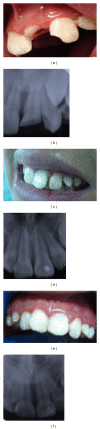

Two cases of young patients with traumatized permanent teeth having complicated crown fractures are reported. Endodontic management included partial pulpotomy by the Cvek technique; restorative management included resin restoration and reattachment of the teeth fragments. Treatments were considered successful in all cases according to the following criteria: absence of clinical symptoms, absence of X-ray signs of pathology, and presence of pulpal vitality 6 to 25 months after treatment.